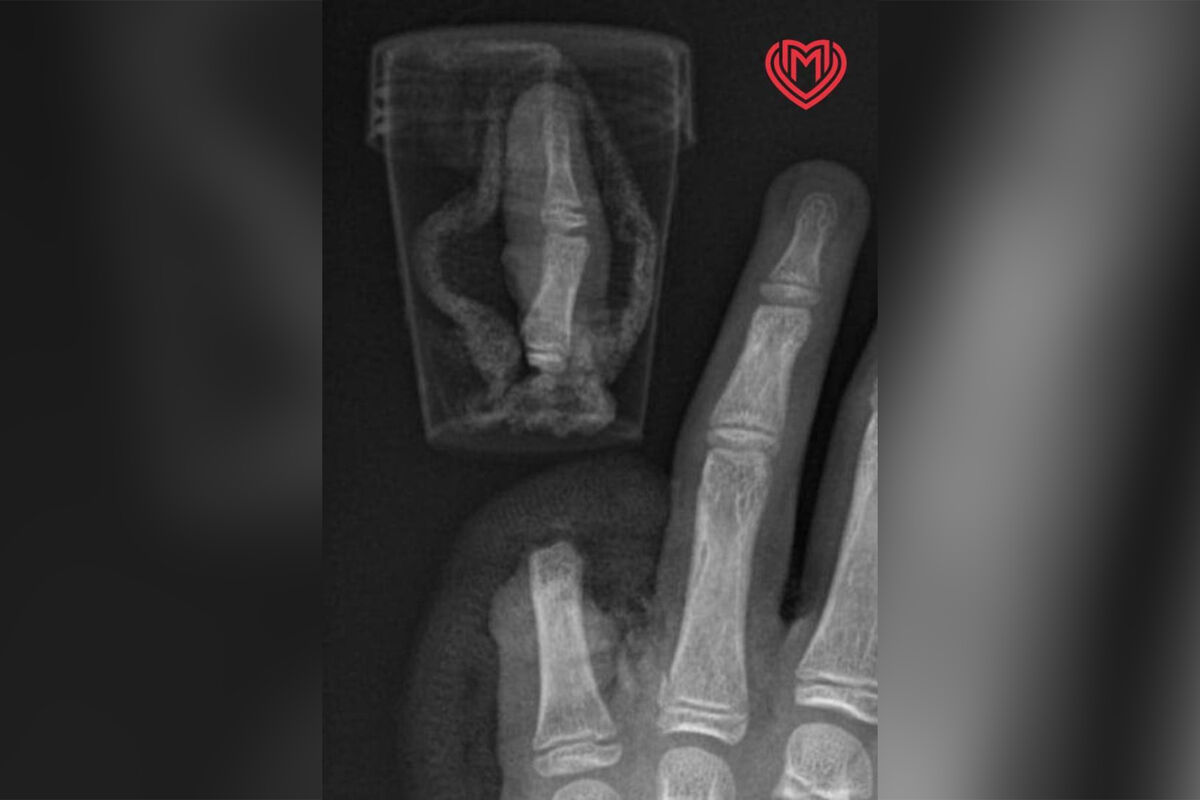

После этого мальчика экстренно госпитализировали в Филатовскую детскую больницу. Медики его осмотрели и приняли решение пришить ему палец на место.

В ходе операции хирурги соединили кости, сухожилия, а также сгибатели и разгибатели мизинца. Затем они сшили нервы и сосуды. Вмешательство прошло успешно и на данный момент ребенка выписали домой, однако он проходит программу реабилитации в больнице. Врачи дают ему благоприятный прогноз на восстановление функции мизинца.